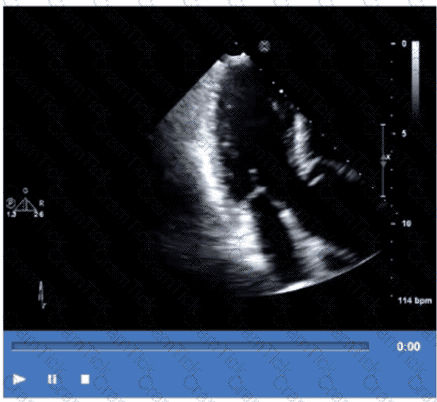

Which step is next in further evaluation of the abnormality shown in this video?

Which is the most likely abnormality represented in these images from a 48-year-old man with shortness of breath?